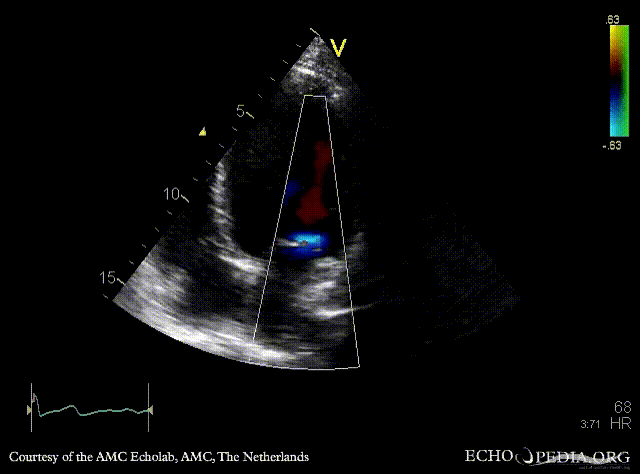

PLAX: Color Doppler, moderate mitral regurgitation A4CH: dilated poor left ventricle